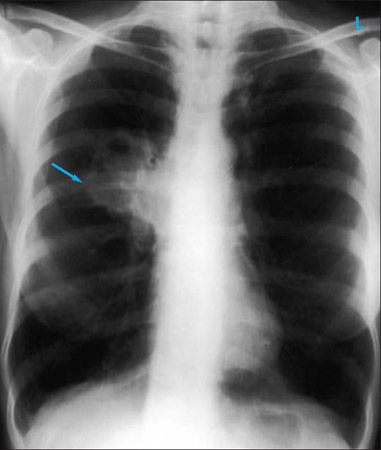

Radiografía de tórax que muestra un carcinoma hiliar derecho cavitante (flecha)

E. Dick, Student BMJ. 2001;9:10-12